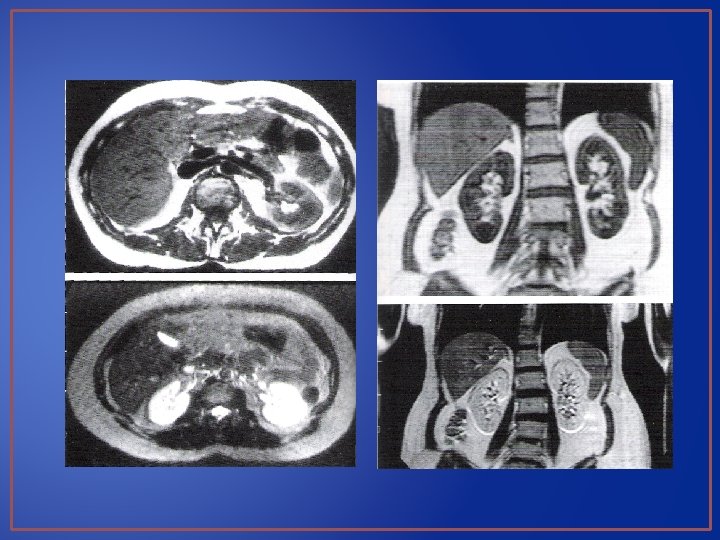

TAC y RMN Aleyda María Soto García

TAC: Indicaciones • Estudio de Masas • Limites, caracteristicas, invasión a tejidos vecinos y metástasis a distancia • Contraste

• Riesgos y Desventajas • Costes relativamente altos de adquisición, instalación, operación y mantenimiento. • Pueden necesitar preparación preliminar de paciente • Equipos son fijos • Ventajas • La obesidad, el contenido del tubo GI y estructuras óseas no interfieren • Excelente demostración anatómica con puntos de referencia visualizados claramente • Examen rápido y detallado: espacio retroperitoneal y cavidad peritoneal • Permite hacer distinción entre las diferentes densidades • Demostración vascular

RMN

• Riesgos y desventajas • Costos elevados de adquisición, instalación, operación y mantenimiento • Conocimiento especializado • Examen prolongado • Sales de gadolinio como medio de contraste • Objetos de metal • Ventajas: • Similares a TC, excepto por factores técnicos. • Alta resolución, buena representación de sistemas colectores sin contraste. • No radiaciones ionizantes